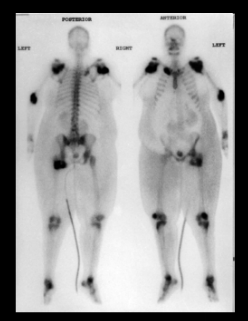

Các xét nghiệm thường bình thường ngoại trừ tăng phosphatase kiềm, tốc độ máu lắng và protein phản ứng C, thường là tăng vừa một vài tuần sau khi khởi phát và là các chỉ báo tốt cho hoạt tính của bệnh. Chụp X quang thường có giá trị chẩn đoán trong các trường hợp rõ ràng. Trong cốt hoá lạc chổ nhẹ và sớm, scan xương ba pha là một công cụ có giá trị để xác định cốt hoá và xét nghiệm này cũng có thể đánh giá sự trưởng thành trong bệnh tiến triển. CT và MRI có vai trò, đặc biệt là để đánh giá trước phẫu thuật để kiểm tra mức độ (lan rộng) của cốt hoá lạc chổ và liên quan với các mạch máu. CT cũng có thể giúp loại trừ các bệnh lý khác như tụ máu hoặc khối u bị vôi hóa.

Hình: Scan xương 3 pha